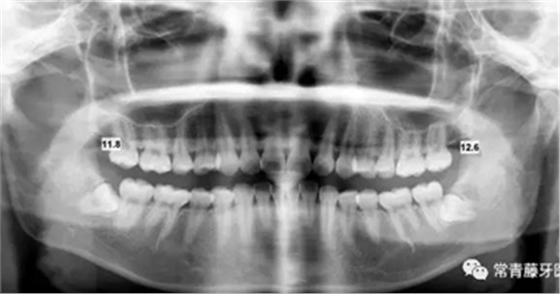

影像學(xué)檢查

曲斷顯示38、48阻生;雙側(cè)TMJ髁突頭略不對(duì)稱。

頭影測(cè)量顯示上下頜骨發(fā)育不足,且呈現(xiàn)骨性Ⅱ類。

曲斷可見牙根基本平行。

(3)全牙列遠(yuǎn)移種植釘植入位點(diǎn)為上頜第一磨牙根上方顴牙槽嵴處,使其與牙根平行,在術(shù)前需CBCT確認(rèn)骨量,否則有脫落或無法植入的可能。